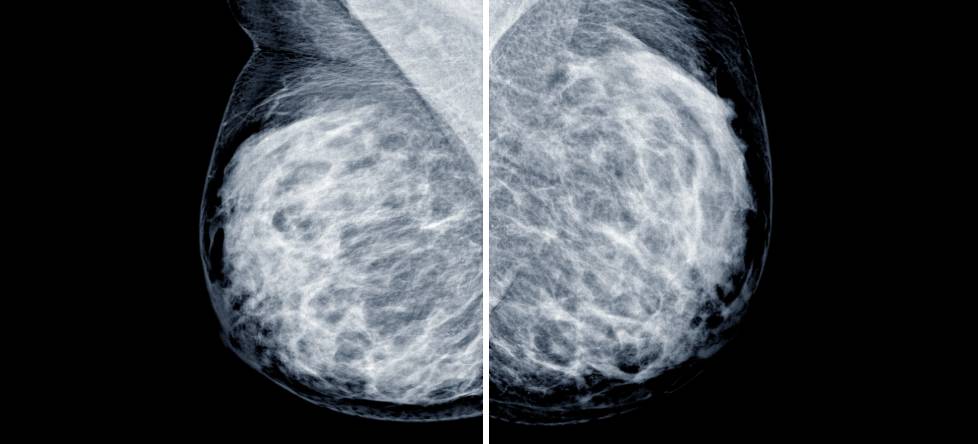

It’s natural to feel overwhelmed, uncertain, or even afraid. Whether you’ve found a lump, been referred after an abnormal mammogram, or are navigating a breast cancer diagnosis, you deserve answers and a care team that listens without rushing.

When a lump is found, a lumpectomy may be recommended to remove it safely and determine whether it’s benign or suspicious. This procedure removes the mass and a small margin of tissue — often preserving the natural shape of the breast.

Depending on the diagnosis, we may recommend a lumpectomy or mastectomy. Our goal is to remove all cancerous tissue while minimizing the physical and emotional impact of surgery, always in coordination with your oncology team.